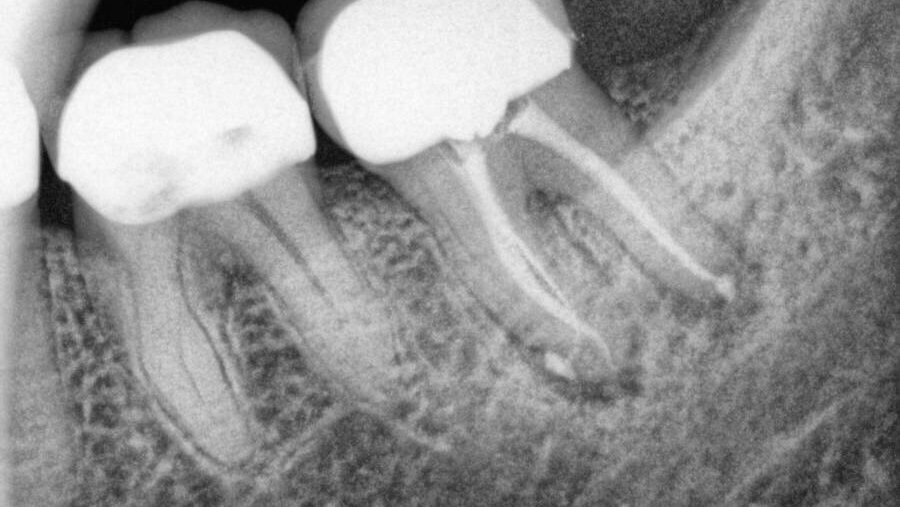

מטרת המחקר הייתה לבדוק השפעת הארכת כותרת ויחסי כותרת שורש על השרידות לטווח ארוך של שיניים עם טיפול שורש

חוקרים מקליבלנד, אוהיו, ביצעו מחקר רטרוספקטיבי על שיניים אחוריות קבועות שקיבלו טיפול שורש ושוחזרו באמצעות כתרים, עם או בלי הארכת כותרת

לאחר חמש שנים, שרידות שיניים ללא הארכת כותרת הייתה גבוהה משרידות השיניים עם הארכת כותרת אם כי לא בצורה משמעותית (89 אחוז לעומת 83 אחוז)

לאחר עשר שנים, שרידות השיניים ללא הארכת כותרת הייתה גבוהה בצורה משמעותית לעומת השיניים ללא הארכת כותרת (74.5 אחוז לעומת 51 אחוז). נמצא ששיניים עם טיפול שורש שעברו גם הארכת כותרת היו בסיכון גבוה פי 2.3 לעקירה לעומת שיניים שלא עברו הארכת כותרת

בנוסף, שיניים אחוריות עם יחסי כותרת-שורש לא תקינים (1:1) לאחר הארכת כותרת הראו את השרידות הנמוכה ביותר (40 אחוז) לעומת שיניים עם יחסי כותרת-שורש תקינים

מסקנת החוקרים הייתה שיחסי כותרת-שורש של 1:1 לאחר הארכת כותרת יכולים להשפיע על השרידות לטווח ארוך של שיניים עם טיפול שורש ויש להביא זאת החשבון בעת תכנון תכניות טיפול